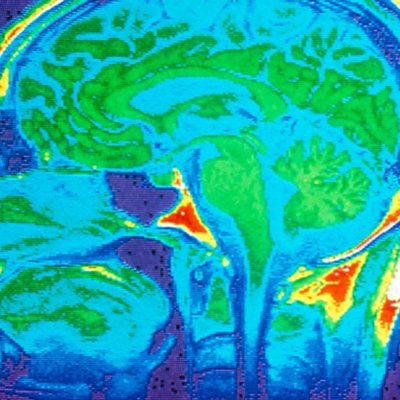

Melvyn Bragg and guests examine the relationship between the mind and the brain as they discuss recent developments in Neuroscience. In the mid-19th century a doctor had a patient who had suffered a stroke. The patient was unable to speak save for one word. The word was ‘Tan’ which became his name. When Tan died, the doctor discovered damage to the left side of his brain and concluded that the ability to speak was housed there. This is how neuroscience used to work – by examining the dead or investigating the damaged – but now things have changed. Imaging machines and other technologies enable us to see the active brain in everyday life, to observe the activation of its cells and the mass firing of its neuron batteries. Our extraordinary new knowledge of how the brain works has challenged concepts of free will and consciousness and opened up new ways of understanding the brain. Yet these new ideas seem to conform to some old ideas such as Freudian Psychoanalysis. But what picture of the brain has emerged, how has our understanding of it changed and what are the implications for understanding that most mysterious and significant of all phenomena – the human mind?With Martin Conway, Professor of Psychology at the University of Leeds; Gemma Calvert, Professor of Applied Neuroimaging at WMG, University of Warwick and David Papineau, Professor of Philosophy of Science at King’s College London.